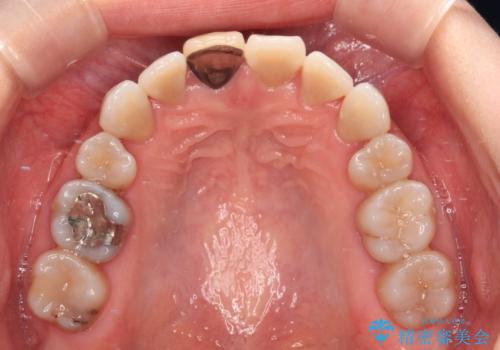

- 結婚式を前に、保険診療での前歯のクラウンが気になるとのことで来院された患者様です。

色合いだけでなく、歯肉の縁が黒くなっていることが分かります。

速やかに仮歯に交換し、オールセラミッククラウンにて補綴することとしました。